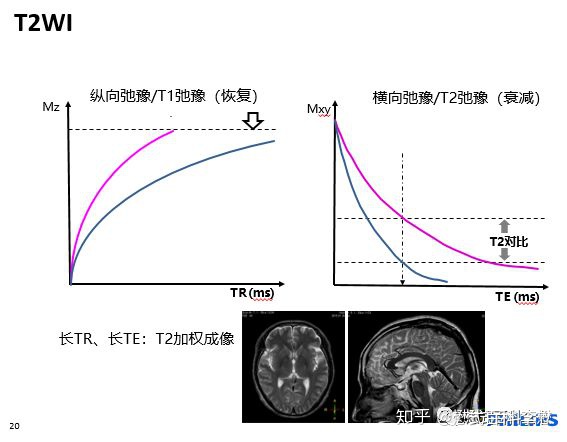

T2加权像(T2WI):主要是反映组织之间T2差别的图像,也就是主要反映组织之间横向弛豫差别的图像;

长TR,长TE,是T2加权像;

TR越长,组织的纵向弛豫恢复越彻底,那么组织之间的纵向弛豫差异(T1)的差异被削弱;TE越长,代表回波时间越长,组织在横向之间的弛豫差异会被拉大,组织的T2差异会越大。(我们可以做一个思维实验,极端情况下,想象TE为0,那么组织之间在横向上的弛豫差异根据就来不及显示,因为TE=0ms,组织之间就没有T2差异了,所以TE越长,理论上组织之间的T2差异越大)。当然,TE也不能无限长,太长以后,所有组织信号全部衰减完了,等于又没有T2差异了。

水(液体)是一种长T1,长T2的组织,这个是液体的特性在参数。

T2越长,在T2WI中,组织的信号强度越高,反映的是图像越白;

T2越短,在T2WI中,组织的信号强度越低,反映的是图像越黑。

脂肪组织是一种短T1,稍短T2的组织,这个是脂肪组织的特质参数。

如上图所示,是一个头颅的T2WI。同前面的分析一样。液体(脑脊液)是长T2的,在T2WI中,应该是高信号,是亮的,所以图中,脑脊液是白色的;而脂肪组织是稍短T2的,在T2WI中,是稍高信号,是白的,所以图中,头皮脂肪也是有点亮的。

这里要注意,脂肪比较特殊,理论上脂肪组织是稍短T2,在T2WI图像上,不应该这么亮。但是目前,磁共振T2WI所有序列均采用TSE进行扫描,因为是TSE序列,随着回波链延长,脂肪组织的信号会升高。